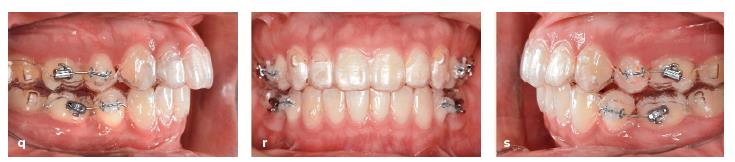

Hình 13-16 (q đến s) Mắc cài phân đoạn được gắn để quản lý nghiêng chân răng vào vị trí nhổ răng.

Do đó, mắc cài phân đoạn được đặt trên các răng hàm nhỏ thứ nhất và các răng hàm lớn thứ nhất để dựng thẳng và làm song song các chân răng tại vị trí nhổ răng. Một cửa sổ được cắt trên khay trong suốt để chứa mắc cài (Hình 13-16q to 13-16s).